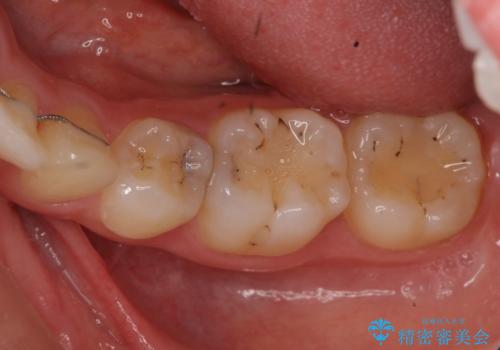

- 奥歯の歯と歯の間が虫歯になっていました。

セラミックインレーで治療しました。